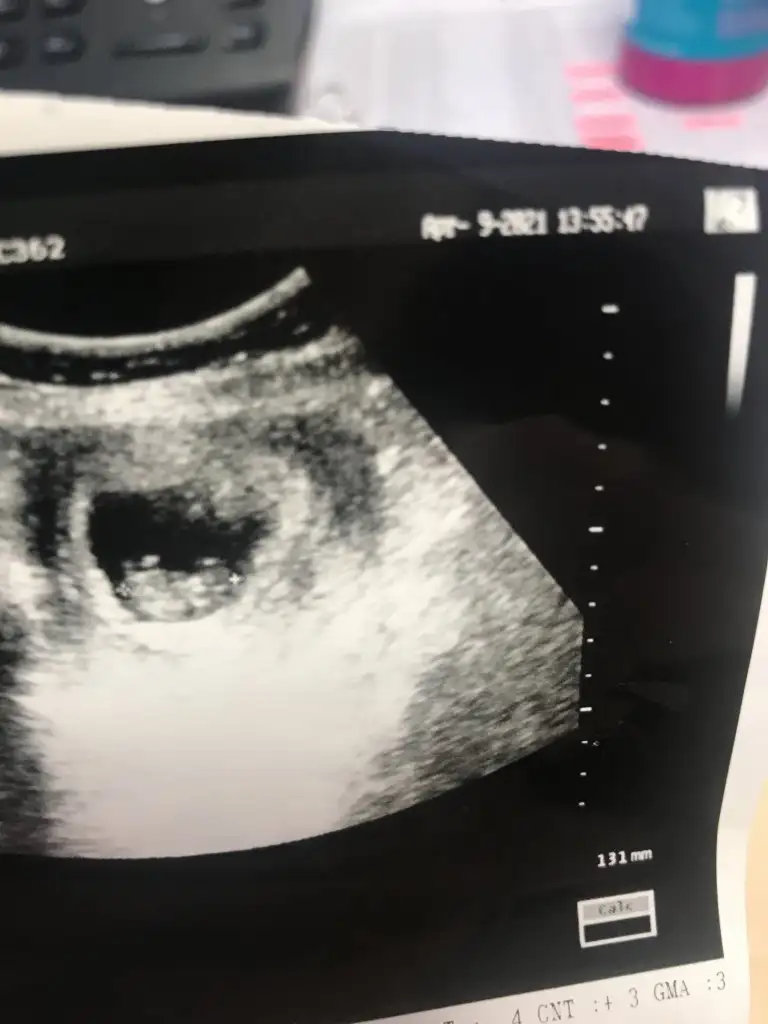

Bu gercekten daha doluOmu doluo dolu ise bu nedir 13 haftaEki Görüntüle 2826253

Erkek görünüyorRica etsem ben de bir tahmin alabilir miyim 11+5 ultrasonu :)

Çok teşekkürler :) Allahim hayırlı evlat versin herkese. Doktorumuz cinsiyetini söylediği zaman hemen yazicam sizeErkek görünüyor